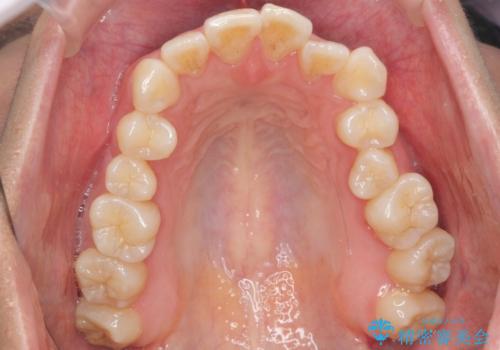

- 前歯の並びを気にして来院。

左上の前歯が内側に入って反対咬合になっていました。

また、左上5番も反対咬合でした。